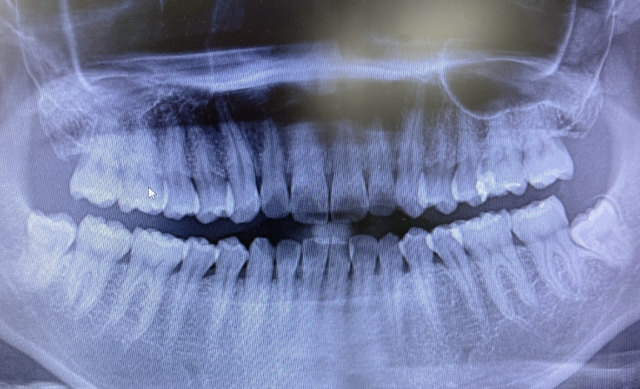

親知らずは口の一番奥に生える大きな歯です。ほとんどの人の親知らずは、17 歳から 21 歳の間に皮膚から生えてきます。親知らずがまったく生えていない人もいます。

場合によっては、親知らずが正しい位置に移動するための十分なスペースが口内にない場合があります。歯肉を斜めに突き破ったり、部分的にしか突き抜けなかったりすることがあります。これが発生すると、 埋伏親知らずと呼ばれ、痛みや感染症などの問題を引き起こす可能性があります。

親知らずが成人期に生えてくると、口の中の他の歯はすでに所定の位置に定着します。口には、4 本の大きな歯が生えるのに十分なスペースがないことがよくあります。

歯が歯茎の途中までしか生えていない場合、食べ物が歯と歯茎の間に挟まりやすくなります。また、これらの歯を清潔に保つことが難しくなり、感染症や虫歯につながる可能性があります。

ただし、親知らずが歯茎を完全に突き抜けて生えている場合でも、問題が発生する可能性があります。斜めに生えていると、口の中や歯茎をこすってしまう可能性があります。他の歯を押して痛みを引き起こす場合があります。

青年期や成人初期に定期的に歯科医院を受診すれば、歯科医は親知らずの生え方を常に監視し、問題がないかどうかを特定できるはずです。